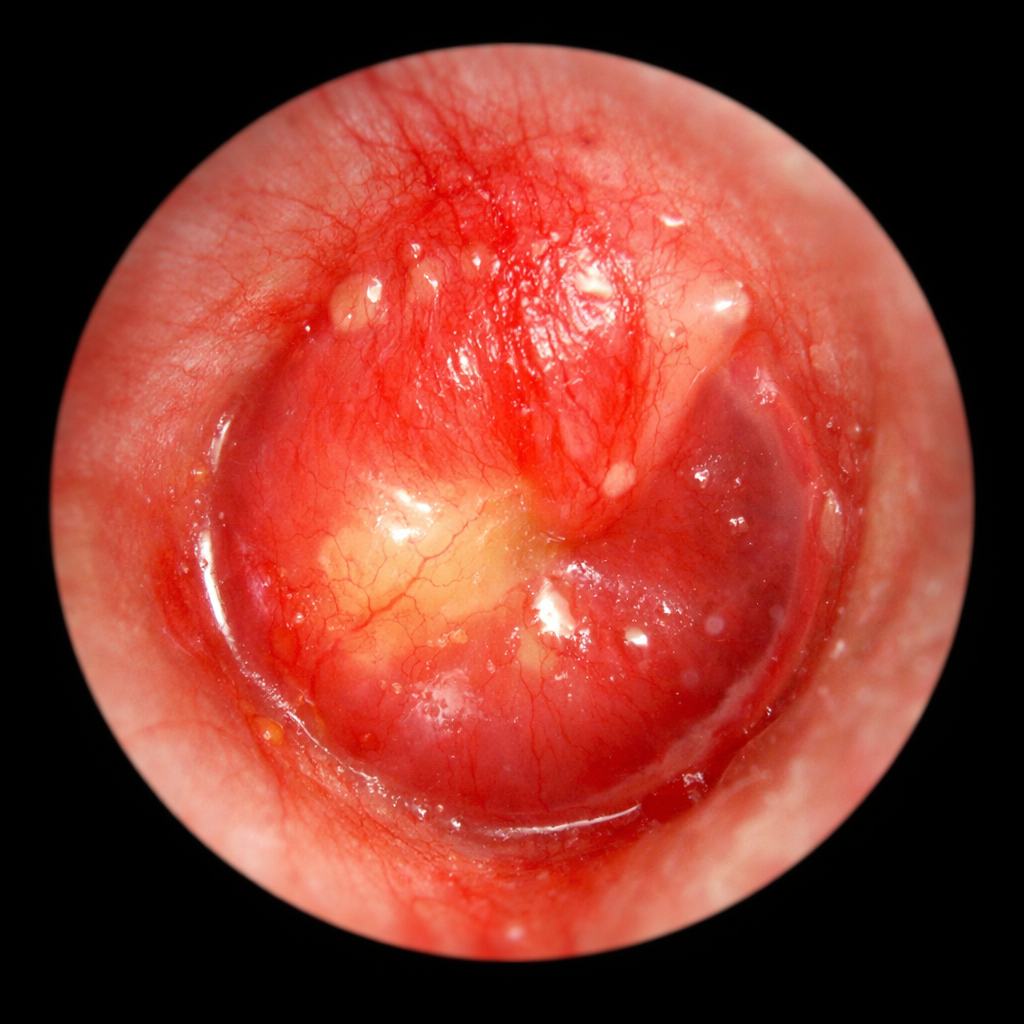

左急性中耳炎

右急性中耳炎の鼓膜所見(AIで作成)

急性中耳炎の鼓膜です。鼓膜が赤く腫れています。